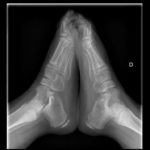

Podología Infantil

Diagnóstico y tratamiento de afecciones en los pies y las uñas, así como la prevención y la cura de la salud podal de los pequeños de casa.

En las etapas de crecimiento y desarrollo de los niños es importante poder diagnosticar de forma precoz posibles patologías y diferenciar las que son propias del crecimiento (pie cavo, pie plano, genu valgo, enfermedad de Sever, marcha en adducción, etc.).

Pie plano infantil